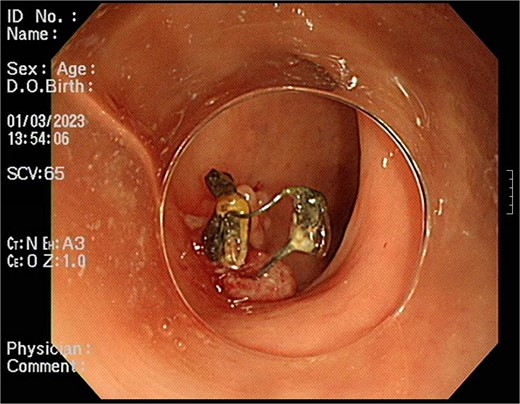

A 54-year-old woman, gravida 4, para 2, presented at the outpatient department with abnormal colonoscopy findings. She had a history of hypertension and underwent an IUD insertion for contraception one year after delivery in 2000. However, in 2007, when she visited the clinic for its removal, the IUD was not found on pelvic examination and ultrasound. The patient assumed that the IUD had been expelled spontaneously. Six months before her 2022 hospital visit, she experienced intermittent rectal bleeding and lower left abdominal pain, leading her to seek medical attention. Her medical history and physical examination, including a digital rectal examination, showed no notable abnormalities except for mild left lower quadrant tenderness. Routine laboratory investigations yielded unremarkable results. During colonoscopy, a foreign body was observed penetrating the sigmoid wall, surrounded by granulation tissue (Fig. 1). Subsequently, an abdominal simple X-ray and computed tomography scan were performed, revealing that the foreign body was an IUD, located next to the left side of uterus and entering the sigmoid colon (Figs 2 and 3).

Foreign body penetrating the sigmoid wall with surrounding granulation tissue observed during colonoscopy.